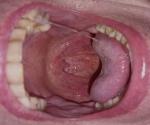

Здравствуйте, Пожалуйста, посмотрите на изображение, в каком состоянии находится мое горло? Уже длительное время по утрам и при глотании у меня болит горло. Нёбные дужки часто красные, а на задней стенке горла есть прыщеподобные бугорки. Правая миндалина тоже увеличена. Я уже несколько раз проходил осмотр у ЛОР-врача, диагностирован хронический фарингит, улучшений нет, к сожалению, мое горло очень слабое с детства. Мой вопрос: чем лечить, как можно окончательно восстановить горло? Спасибо.